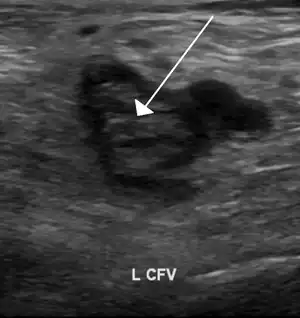

An ultrasound image demonstrating a blood clot in the left common femoral vein.

Thrombophilia (sometimes called hypercoagulability or a prothrombotic state) is an abnormality of blood coagulation that increases the risk of thrombosis (blood clots in blood vessels).[1][2] Such abnormalities can be identified in 50% of people who have an episode of thrombosis (such as deep vein thrombosis in the leg) that was not provoked by other causes.[3] A significant proportion of the population has a detectable thrombophilic abnormality, but most of these develop thrombosis only in the presence of an additional risk factor.[2]